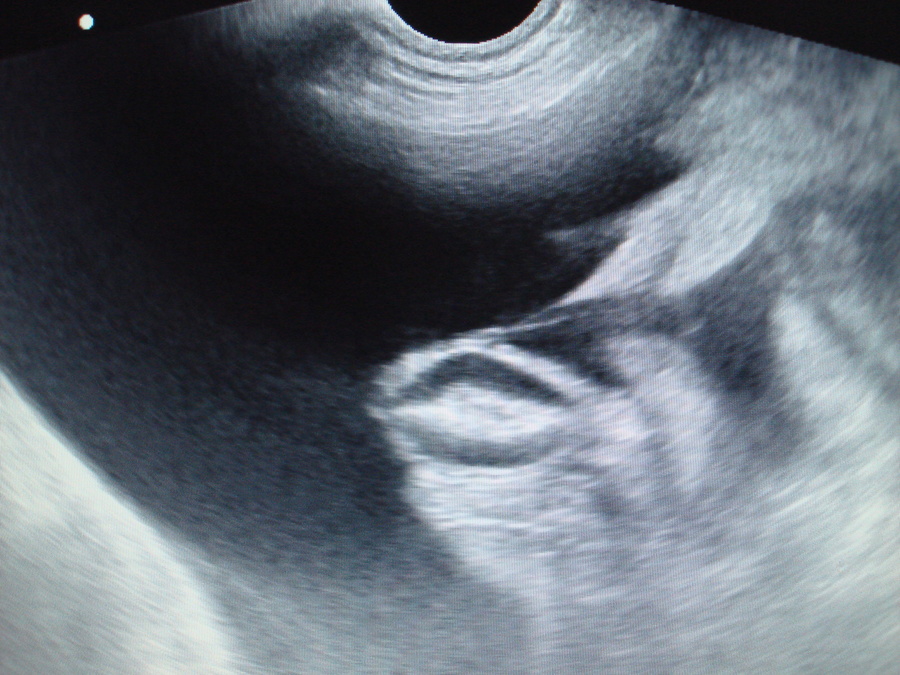

Na tomto sonografickém snímku je zachycena volná nitrobřišní tekutina (černě zbarvená plocha) a v ní plovoucí klička tenkého střeva.

Hemoperikard-SONO břicha-peritoneální efuze2